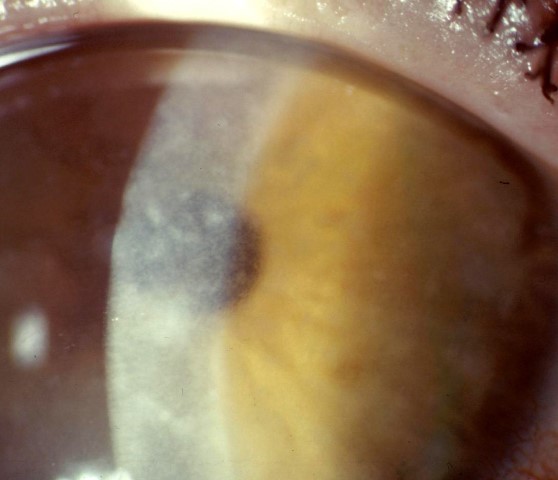

GCD1 is characterised by bilateral deposits in the anterior central stroma appearing as small, discrete, well demarcated, greyish-white opacities, typically appearing during the first or second decade of life. The deposits may first appear as fine dots which later take on a crumb-, ring-, or drop-shaped appearance. These lesions progressively increase in size, number, and may coalesce. Further advancement sees a ground-glass appearance of the cornea develop between lesions. In the early stages, patients normally suffer no discomfort or visual changes, although a subset does suffer erosive episodes. By the fourth decade, visual impairment can begin, typically secondary to opacification of the intervening stroma (Fig 1).

Fig 1a. Central crumb-like stromal deposits with clear intervening stroma

Fig 1b. Confluent breadcrumb granular opacities under direct and retro-illumination

Fig 1c. GCD1 in the same family, with large peripheral-sparing grey-white opacities in the father

Fig 1d. GCD1 in the same family, with a much finer, granular appearance in the daughter.

Credit: Prof McGhee